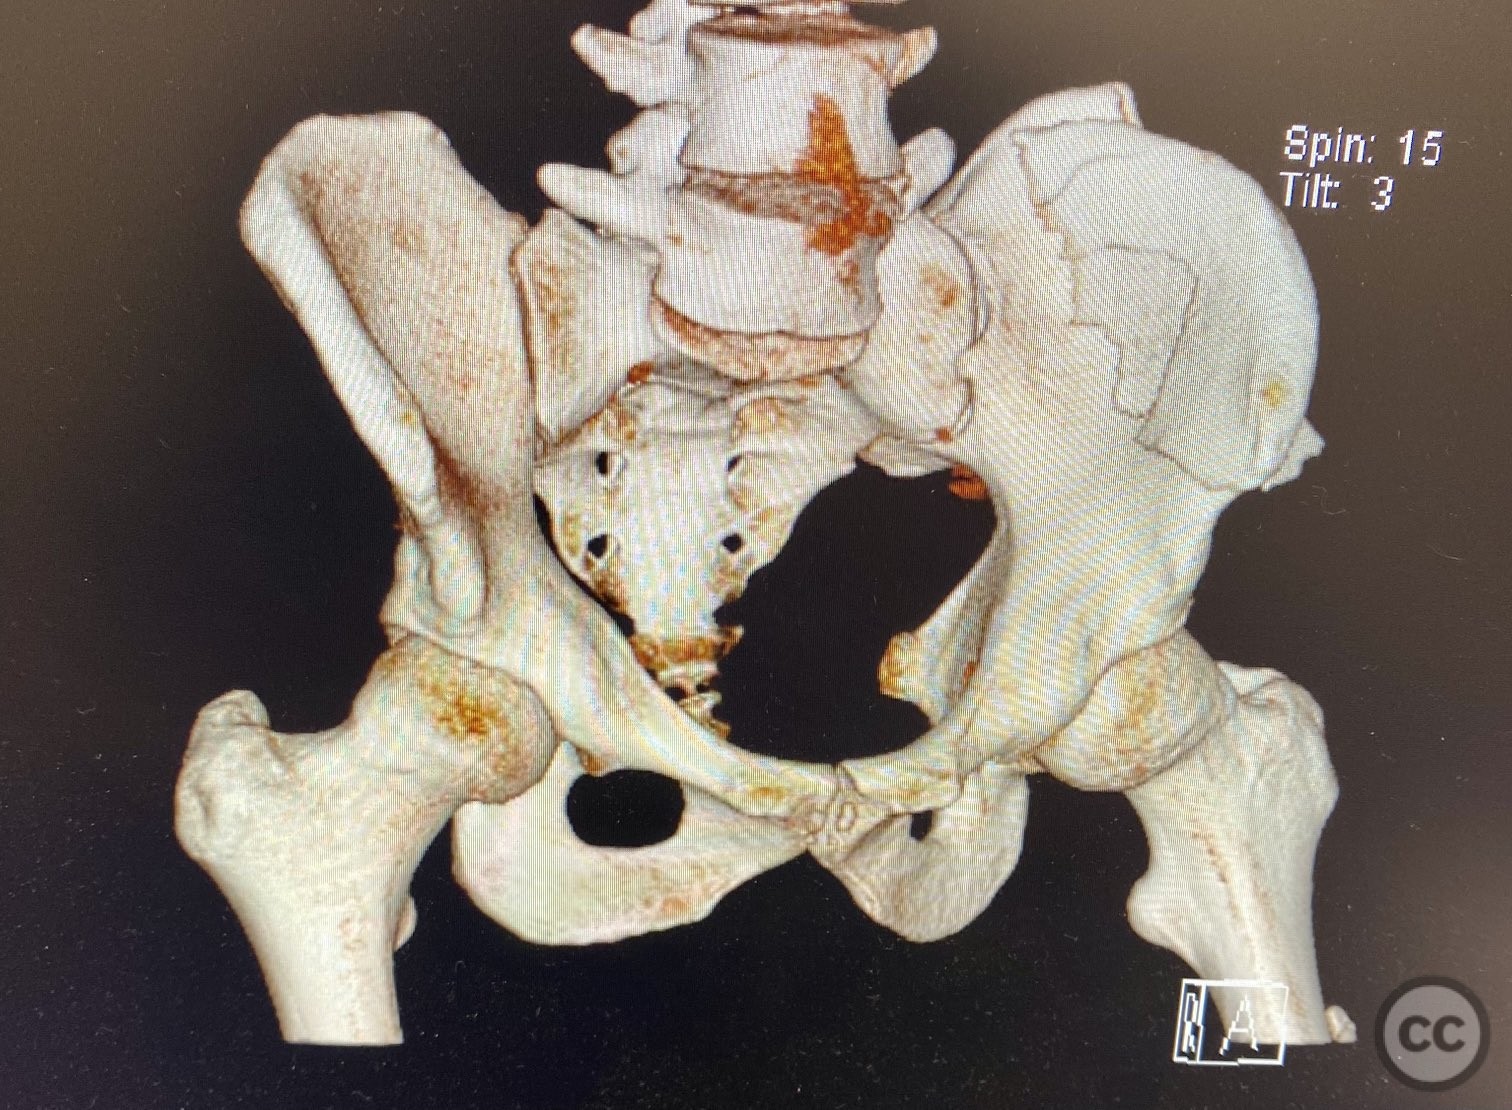

Clinical and radiological findings:  A patient sustained a high-energy injury resulting in an open, comminuted fracture of the iliac wing, sparing the pelvic ring. Associated injuries included spine, rib, and femur fractures. Initial radiographs and axial CT imaging demonstrated significant comminution of the iliac wing with intraosseous air densities indicative of an open wound. No pelvic ring disruption was identified. AO/OTA classification: 61-A2. The presence of multiple associated injuries is consistent with a direct lateral load mechanism.

Preoperative Plan

Planning remarks:  The preoperative plan included emergent irrigation and debridement of the traumatic open wound, followed by anatomical exposure of the iliac wing for further irrigation and debridement. Fracture stabilization was planned using lag screw fixation between the iliac cortices to minimize implant prominence and reduce infection risk.

The comminuted nature of the fracture required careful sequential reduction of multiple small fragments. Given the open nature of the injury and risk of contamination, meticulous irrigation and debridement were performed both through the traumatic wound and via surgical exposure. Lag screw fixation was selected to minimize hardware prominence and reduce surface area for potential infection. The traumatic wound was closed primarily with sutures due to satisfactory soft tissue condition; surgical incisions were closed in layers over drains.